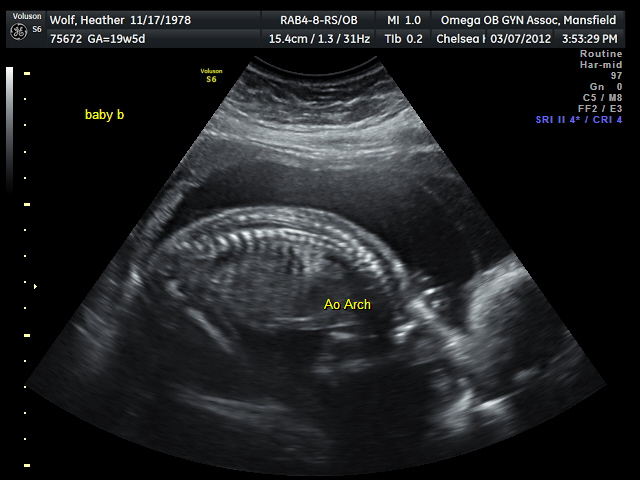

Baby Boy - 12oz - 9" long

| profile of our Baby Boy (he's a little more camera shy) |

| a cool shot of Baby Boy's spine |